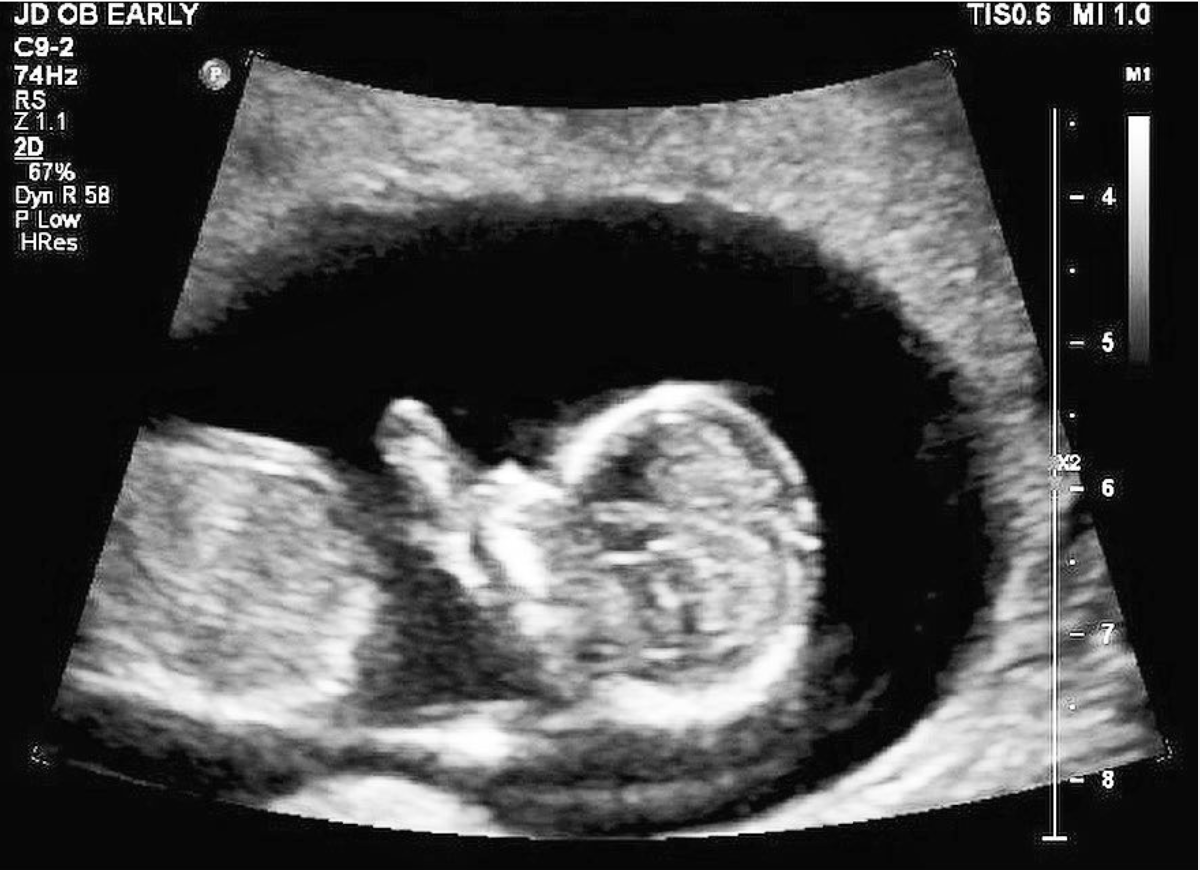

Yep! I’m pregnant!

2019 is set to be the best and biggest and most crazy year yet! In June Dom and I are going to become parents!